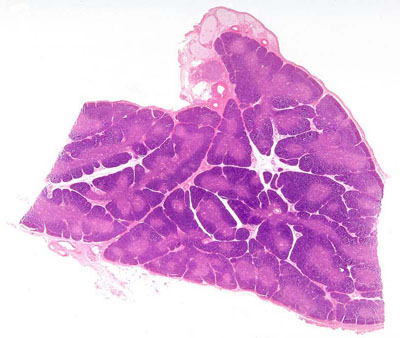

El apéndice se proyecta desde el extremo cerrado del ciego.Su luz es amplia y permeable en la infancia, pero con la edad puede llegar a obstruirse.En este órgano podemos encontrar un epitelio de revestimiento muy parecido al del colon con abundantes nódulos linfáticos.Recuerda que la obstrucción de la estrecha luz del apéndice puede provocar una apendicitis (una inflamación que cursa con dolor en la fosa ilíaca derecha).Una característica distintiva de la pared del apéndice es la presencia de una gran cantidad de folículos linfoides en la mucosa y la submucosa.En el apéndice también pueden aparecer tumores benignos y malignos los más frecuentes se conocen como tumores carcinoides. (No se observan en la imagen)El apéndice forma parte del tejido linfático asociado a la mucosa intestinal (GALT) que interviene en la defensa inmunitaria. En los centros germinales de estos folículos linfoides se producen los Linfocitos B.